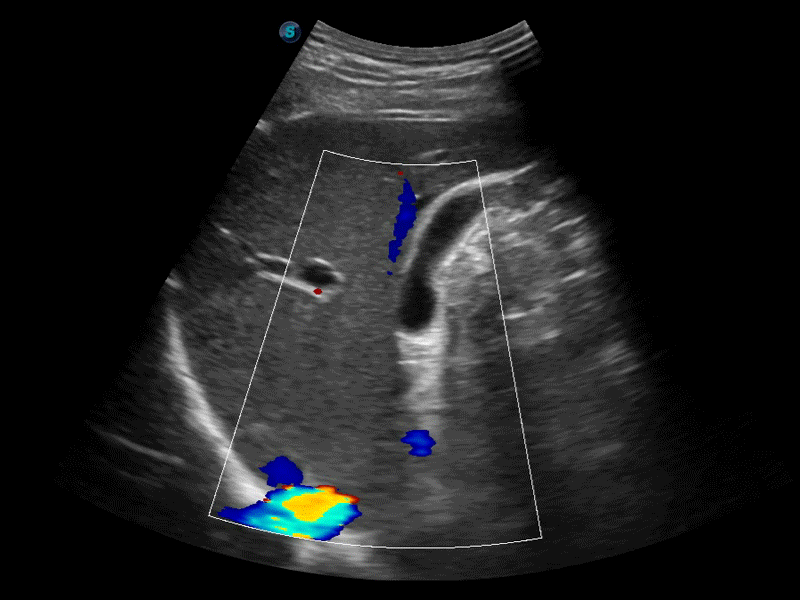

凸陣、線陣和相控陣探頭進(jìn)行實(shí)時(shí)掃描時(shí),開(kāi)啟擴(kuò)展成像模式,可以擴(kuò)展超聲圖像視野,以便更完整地查看大的病灶或組織器官的解剖結(jié)構(gòu)。

通過(guò)色彩血流和實(shí)時(shí)寬景相結(jié)合,可觀察到完整的靜脈或動(dòng)脈的血流,方便醫(yī)生檢查。實(shí)時(shí)掃查過(guò)程中,如有任何操作失誤也可以很容易地進(jìn)行回掃擦除,而不會(huì)中斷掃查。